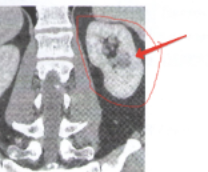

Подхватил я его, скорее всего, на последней операции в августе 2023, до этого все анализы чистые были. В июне 2024 на контроле были сильно повышенные АСТ/АЛТ, с тех пор и начали искать, вот нашли...

Пока тока сам вирус и туева хуча антител. Генотипирование еще в процессе, через неделю будет готово.

Есть смысл паниковать и покупать индийские таблетки или можно ждать? (печонка в норме по УЗИ и КТ с контрастом) Что с побочками у индусов?